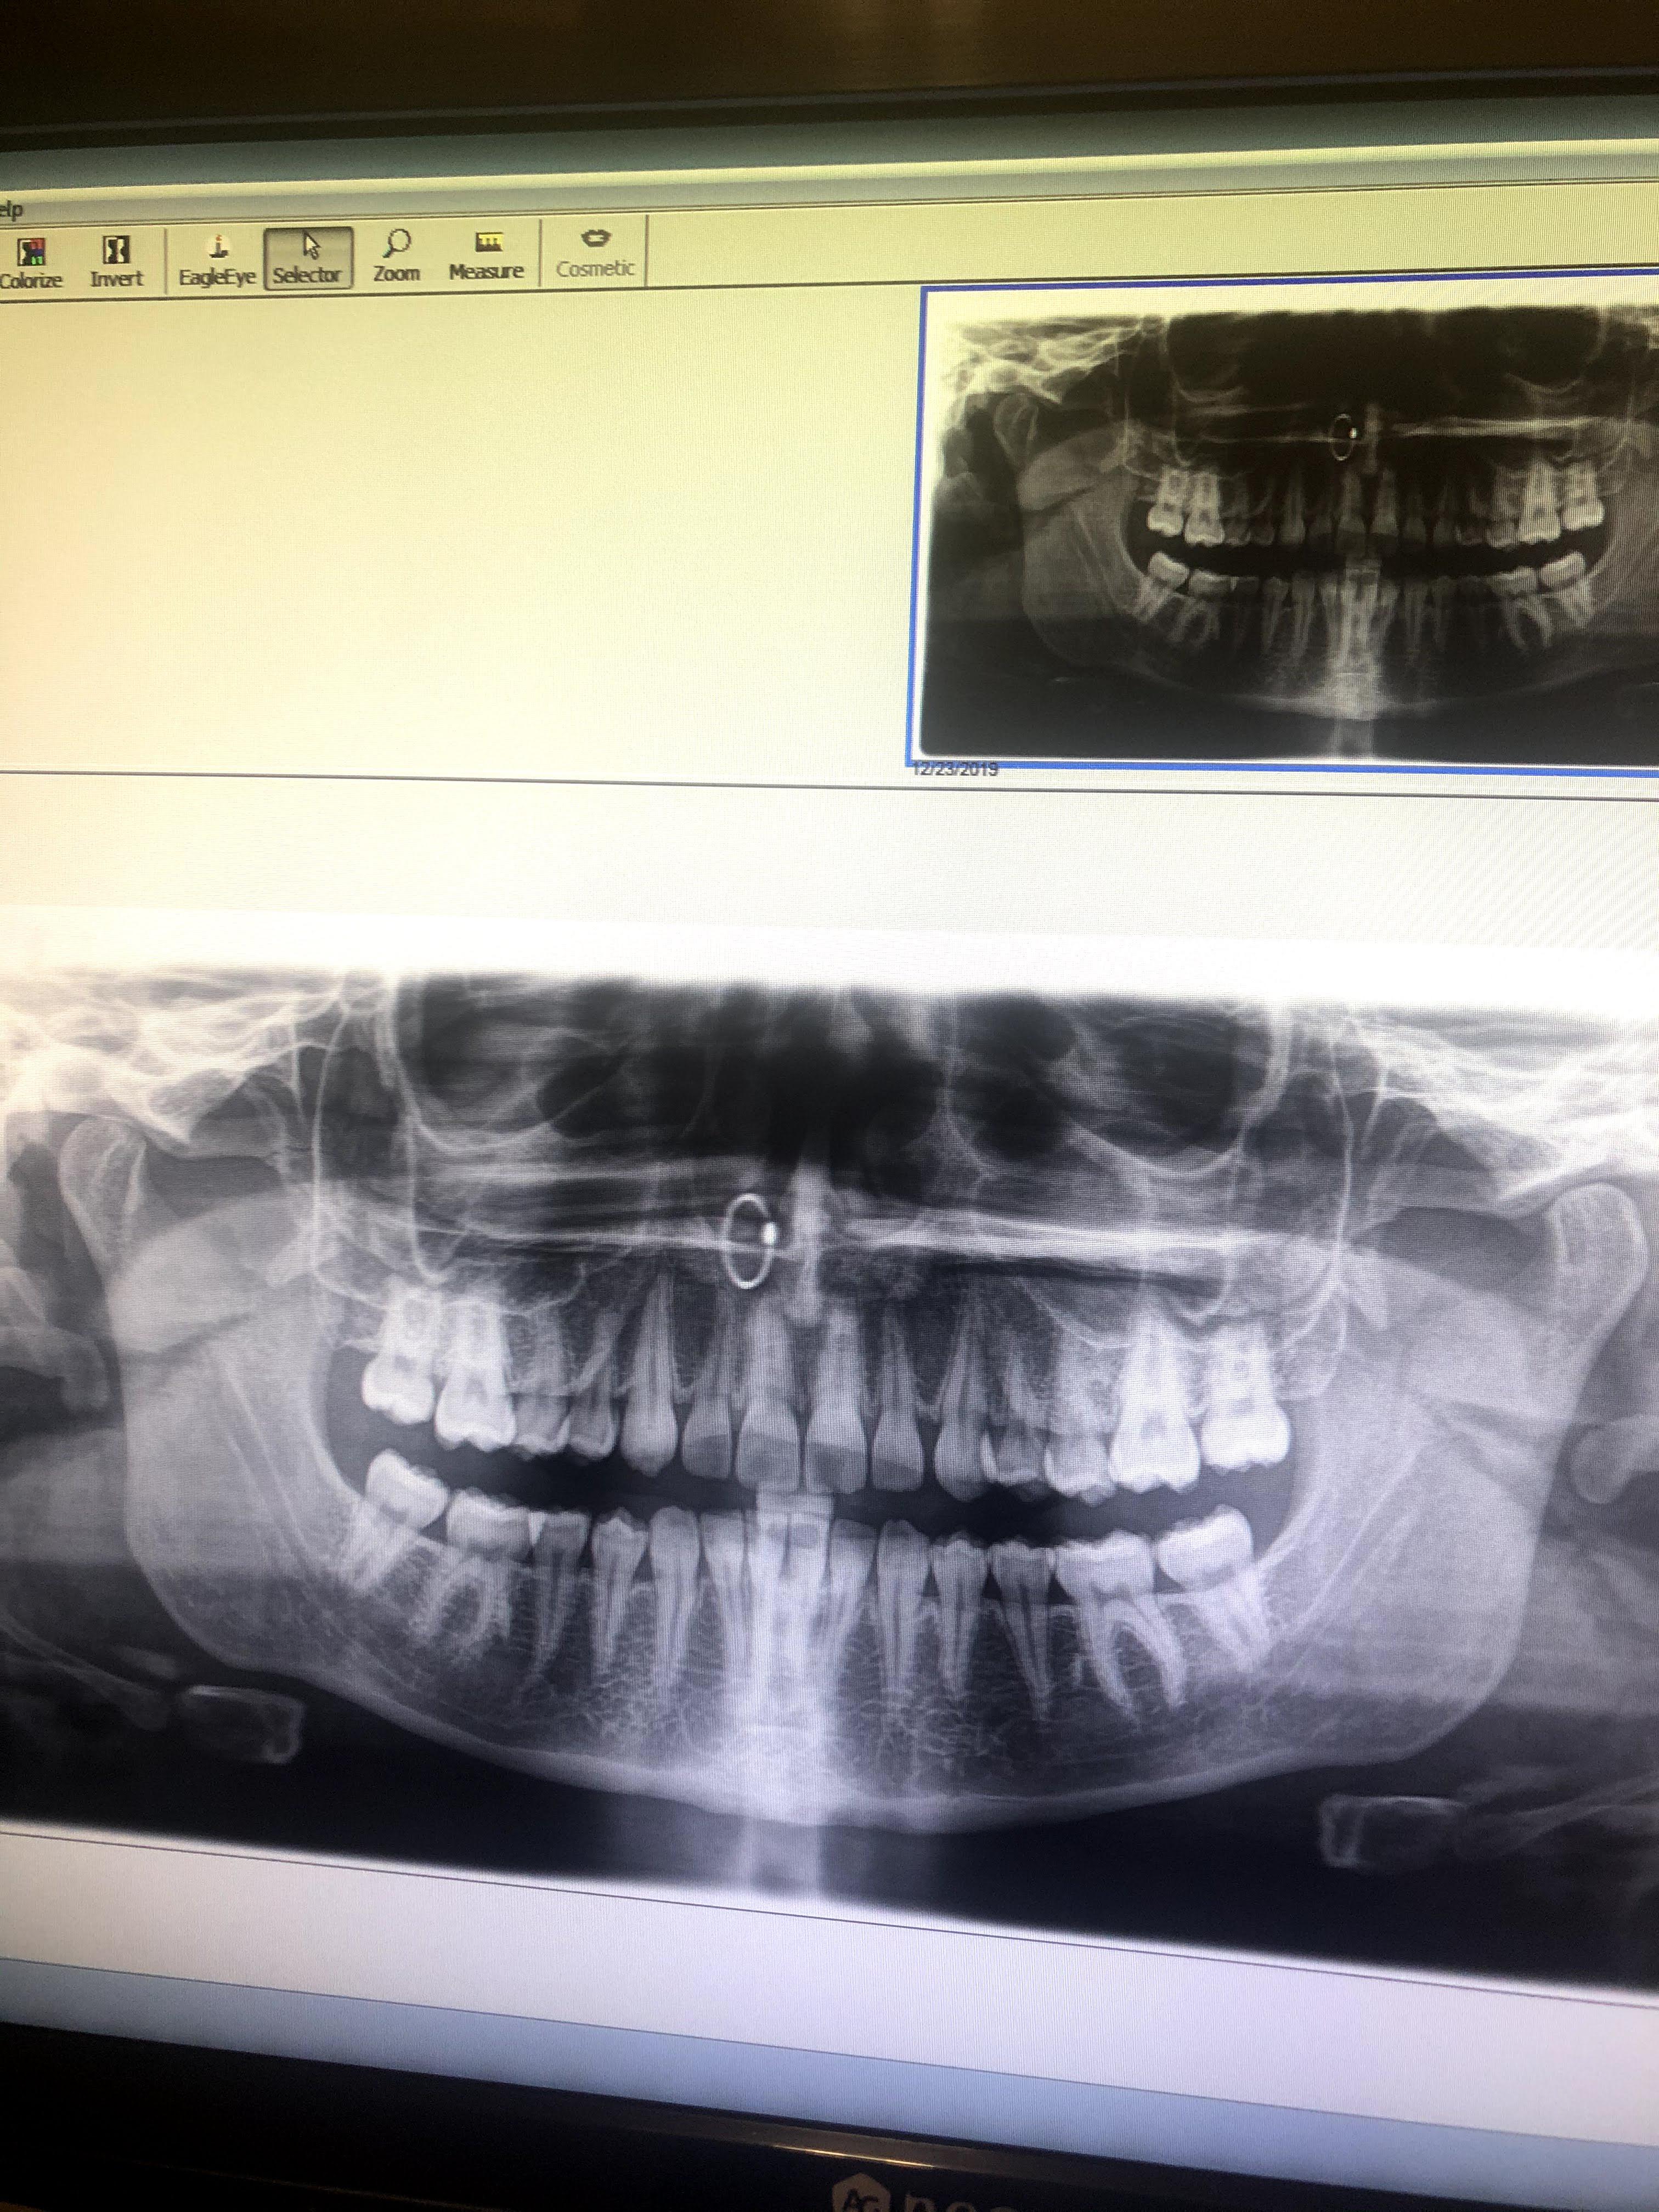

Nose Ring Dental X Ray Contact us for costs and all types of x. For extra oral they ideally should be taken out but. As for record keeping, a dentist may. However its up to the clinician to. For intra oral ones then they can be left in. Contact us for costs and all types of x. The nose ring will appear on the xray in an area that can block a possible tooth image.

You can see my nose ring in my dental xray. r/mildlyinteresting Nose Ring Dental X Ray For intra oral ones then they can be left in. As for record keeping, a dentist may. However its up to the clinician to. Contact us for costs and all types of x. For extra oral they ideally should be taken out but. The nose ring will appear on the xray in an area that can block a possible tooth. Nose Ring Dental X Ray.